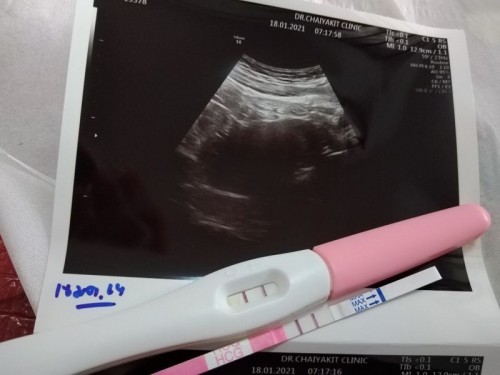

ตรวจขึ้นสองขีดมีเลือดออกซาวไม่พบเด็ก

สอบถามคุณแม่หน่อยค่ะ ก่อนหน้านี้มีเลือดออกเหมือนประจำเดือนประมาณ1อาทิตย์มีคนทักว่าเป็นเลือดล้างหน้าเด็กเราซื้อที่ตรวจมาตรวจปรากฏว่าขึ้น2ขีดเราเลนไปหาหมอที่คลินิกฝากครรภ์หมอซาวไม่พบอะไร นัดอีกทีวันที่25 หมอบอกว่าอาจจะแท้งไปแล้ว อาการแบบนี้แม่ๆเคยเจอแล้วไม่ได้แท้งไหมค่ะ คือเราอยากมีลูกมากปล่อยมา8ปีแล้วค่ะ #ขอคำแนะนำหน่อยค่ะ #ขอบคุณล่วงหน้านะคะสำหรับคำตอบ

เราขึ้น 2 ขีดเข้มๆเลยคะ มีเลือดสีน้ำตาลออกตลอดตั้งแต่ก่อนตรวจครรภ์เอง จนไปหาหมอ ซาวน์ครั้งแรกผ่านทางช่องคลอด เจอถุงตั้งครรภ์แต่ไม่เจอเด็ก หมอให้ 2 ข้อ คือ 1. อายุครรภ์ยังน้อย 2. ท้องลม หมอนีดอีกครั้ง 2 สัปดาห์ มาตรวจอีกครั้ง อายุครรภ์ 7 สัปดาห์ 1 วัน ซาวน์ช่องคลอดเหมือนเดิม เจอเด็ก หัวใจเต้น รกเกาะติดดี คุณหมอแจ้งว่า จากภาพที่ซาวน์ เส้นเลือดฝอยด้านในแตก + เลือดเก่าที่ค้างอยู่ สรุปรวมๆ เลือดล้างหน้าเด็กคะ บางคนมา 1-2 วัน บางคนมาเหมือนเป็นประจำเดือนคะ